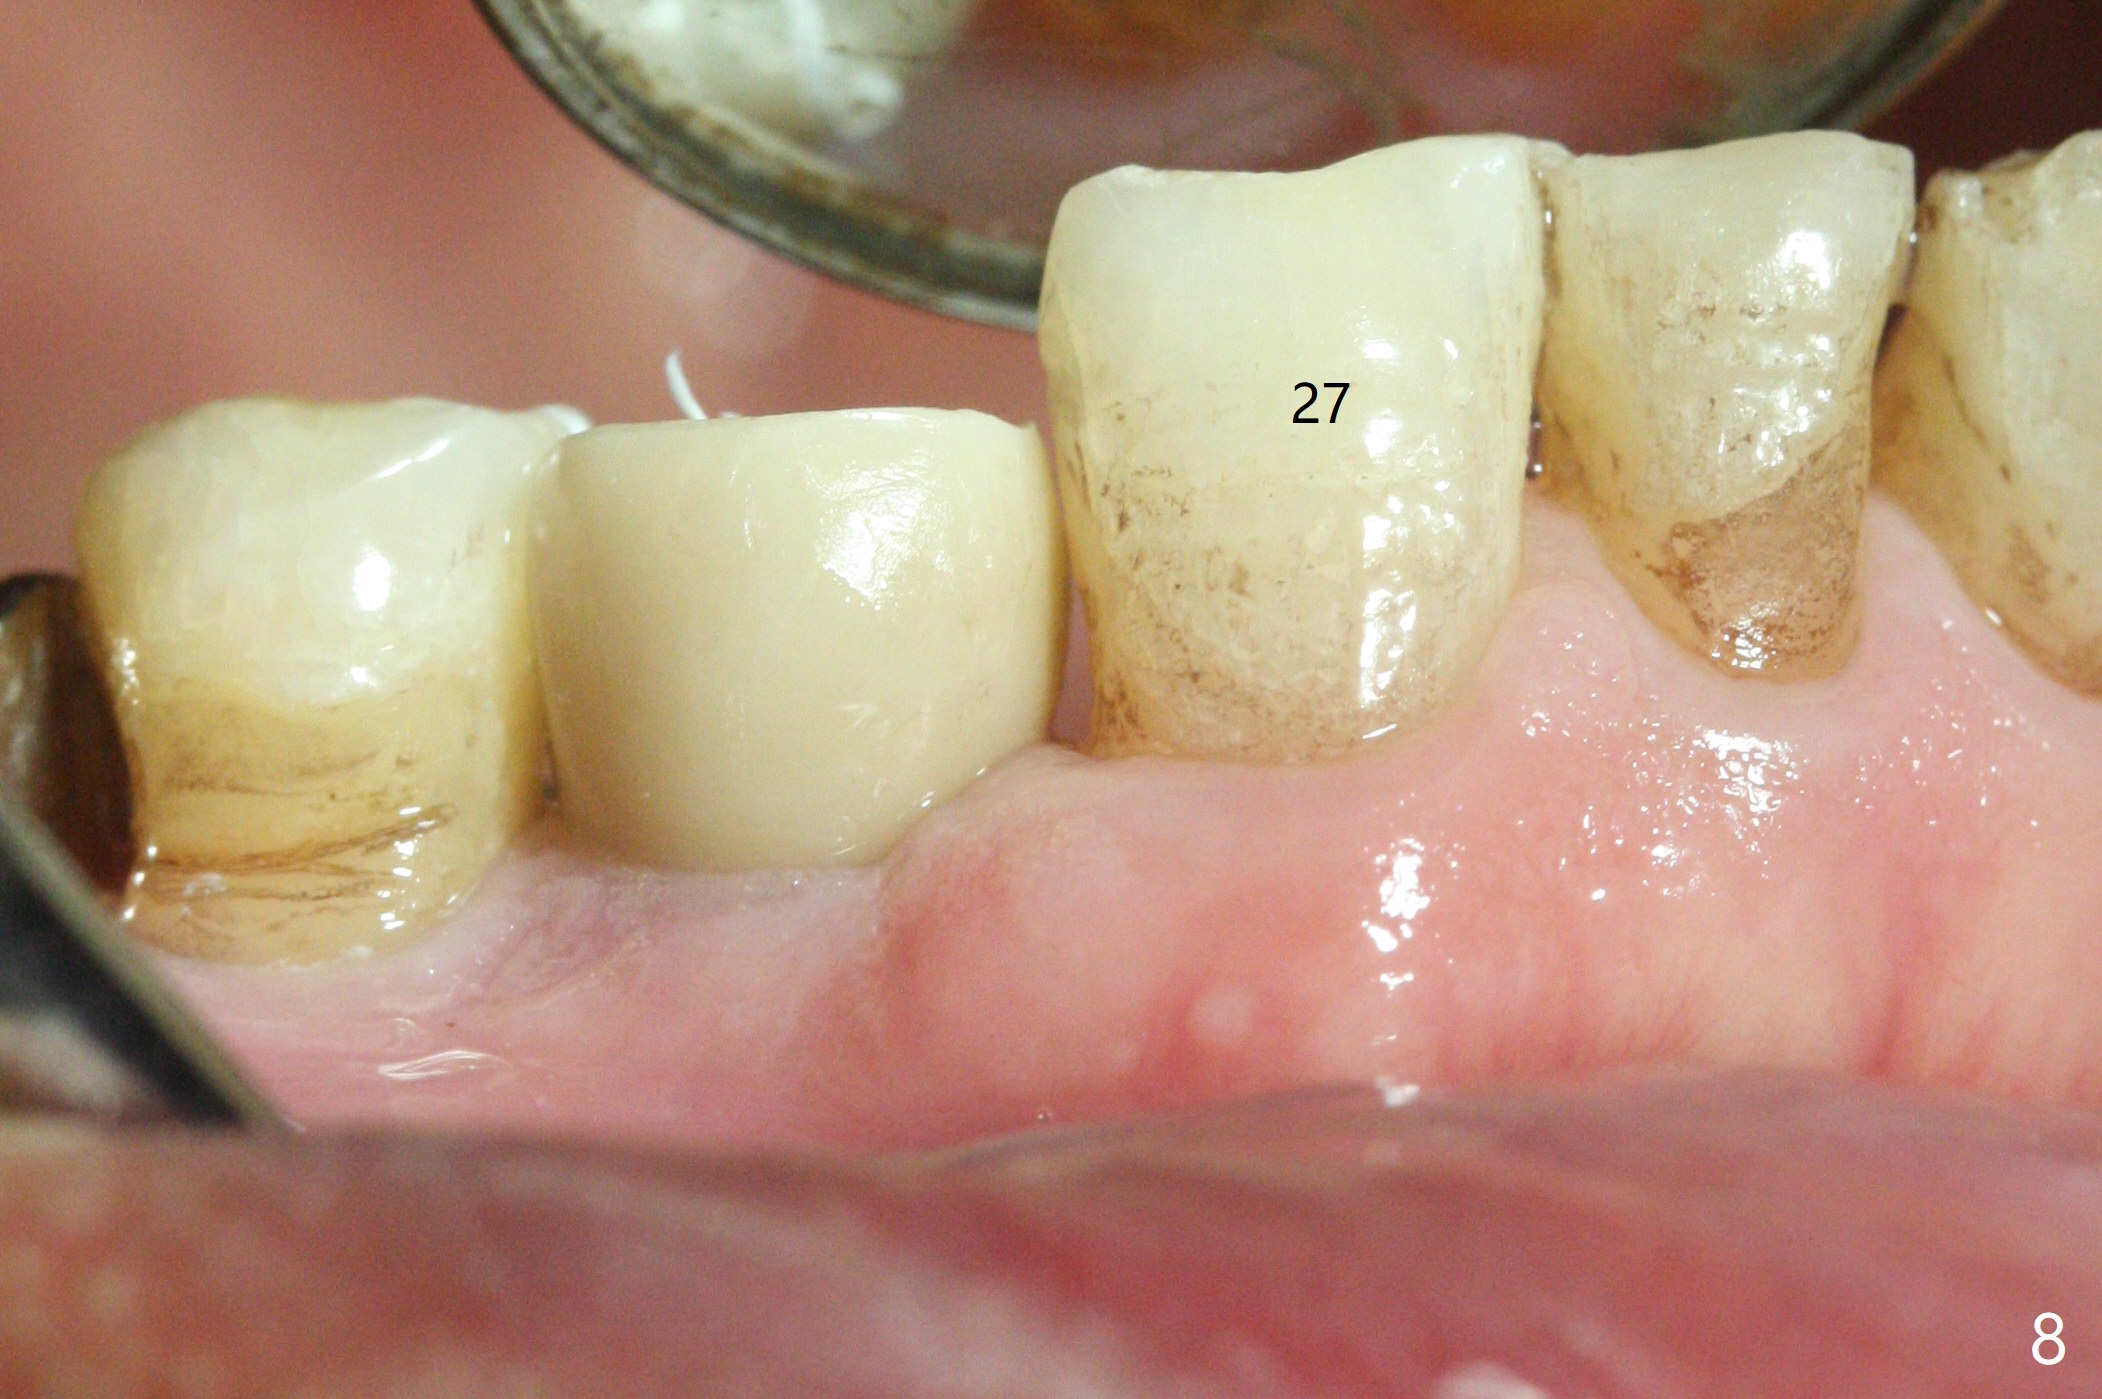

In fact the mesiodistal space of the site of #28 is within normal limit. The buccal plate atrophy is striking (Fig.1) with a fistula (^, associated with underlying residual root tip). When the flaps are raised, the ridge is triangular with the lingual plate (Fig.2 *) higher than the buccal one. Because of the slope, the multiple-drill approach is adopted in stead of single-drill one, because the marking bur is wobbling after 1.6 mm osteotomy at 13 mm (Fig.3). After placement of a 4x11 mm implant, a 4.5x4(2) mm abutment is inserted (Fig.4). The abutment and the implant act as a mesh (framework) so that bone graft and collagen membrane can be laid upon them buccolingually. When the flaps are sutured, there is less tension than that without the abutment. Furthermore, the buccal tissue volume seems to be increased (Fig.5 (<: fistula, which should heal soon), as compared to Fig.1). Tale photos to show effectiveness of the simultaneous GBR and disappearance of the fistula. Three months postop (Fig.6,7 (incomplete abutment seating)), the implant is loaded for intrusion of the opposing supraerupted tooth. The patient returns with chief complaint of food impaction between #27 and 28 three years 7 months post cementation; there is an open contact. Before pick up impression the distal convex surface of #27 is trimmed. The repaired crown has tight proximal contacts before (Fig.9,10) and after (Fig.11) retightening and cementation.